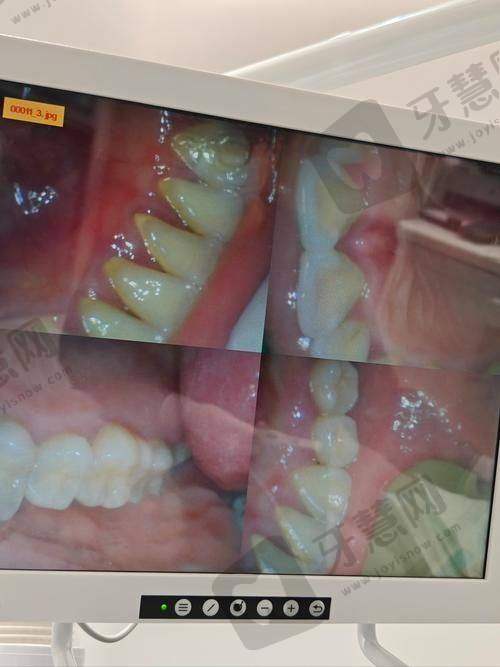

设备仪器:配备了精良的设备仪器,如CBCT机、全景机、超声洁治器、急救设备、烤瓷炉、根管填充器、激光设备、电动吸引器、口腔内窥镜、iTero口内扫描仪、高温高压消毒设备、热牙胶充填设备、超声骨刀等,为精细诊断和有效治疗提供有力保护。

厦门百姓口腔医院在业内拥有良好的口碑和较高的认可度。从患者反馈来看,许多患者对医院的服务和治疗成效给予高度评价。有患者表示,面诊多家牙科后,百姓口腔推荐的牙齿贴片便宜又好,解决了大小牙、牙齿不白等问题,感觉特别良心。还有患者在接受前牙根管治疗后,称赞医院环境干净整洁,医生十分正规,耐心解释每一个治疗步骤,术后回访也特别贴心。在行业内,医院凭借精良的设备、专精的医生团队和优质的服务,在当地人分享的厦门牙科医院实力排名中占据一定位置,其牙齿矫正、牙齿修复等项目更是得到广泛认可。